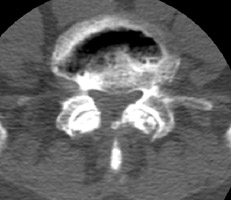

Degenerative disk disease

The presence of a linear radiolucency in the disk space (vacuum phenomenon) is a typical finding of degenerative disk disease. It is often associated to other findings of degenerative disk disease such as disk space narrowing and endplate sclerosis. Gas in the disk space is rarely associated to disk space infection.